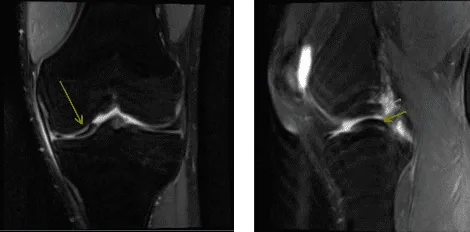

MRI of left knee

After a week the patient returned for follow-up with an MRI result. It showed an impression of abnormal morphology of the ACL likely related to partial disruption or possibly complete disruption and Medial meniscus bucket-handle tear.